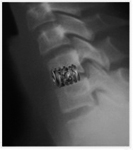

- In allen anderen Fällen wird durch einen kleinen Hautschnitt von 2-3 cm der Wirbelkanal dargestellt.

- Unter dem Operationsmikroskop wird der Nerv weggehalten und das herausgesprengte Bandscheibenmaterial entfernt.